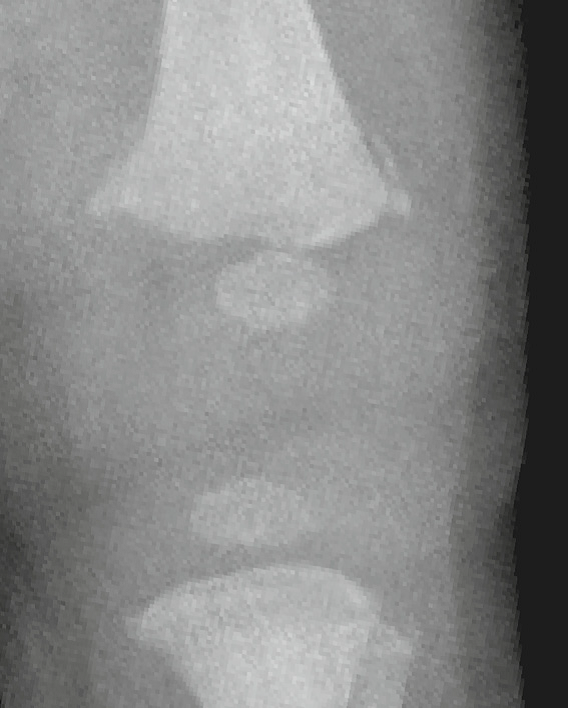

Osgood-Schlatter lesion

aka Tibial tuberosity avulsion

Chronic avulsive injury of the patellar tendon at its inferior attachment

Findings:

• bony fragmentation of the tibial tubercle/tuberosity

• thickening and indistinctness of distal patellar tendon

• associated soft tissue swelling

How well did you know this?